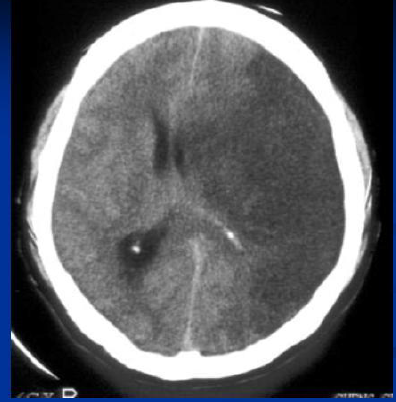

Q

מהו הממצא שבתמונה

A

חסימה מלאה של ה

MCA

עם דחיקה של המיספרה ימין